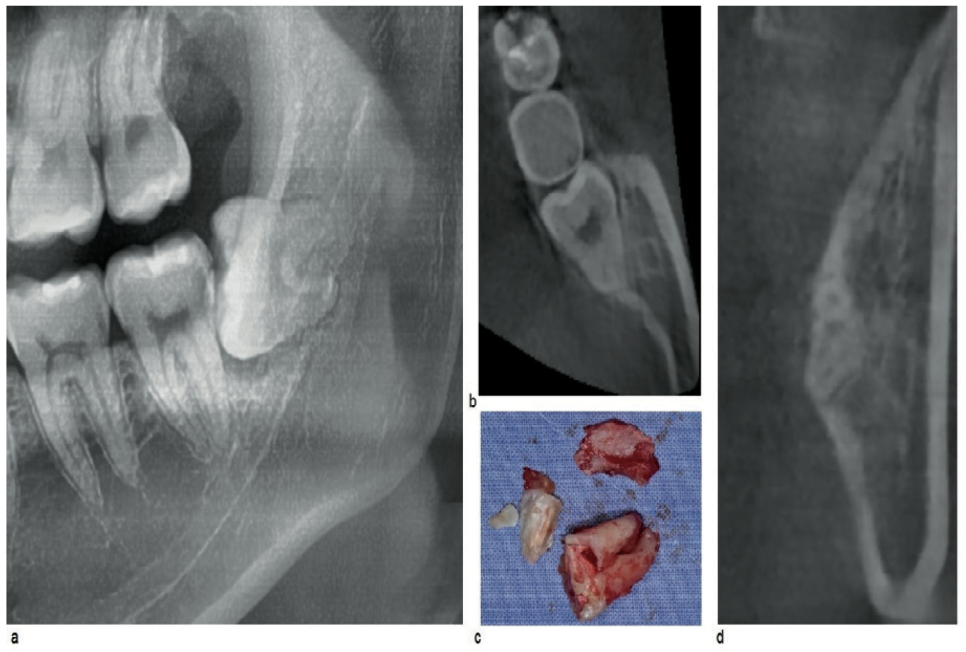

두번째 사례는

제3대구치의 치관부분이 뼈와 근접함

이렇게 파노라마 상에

사랑니 주변에 어두운 영역이 발견되면

여러가지 원인을 파악해보아야 된다.

뿌리주변 병변

미성숙한 치근단

하치조신경과의 관계

피질골에 뿌리 함입

이러한 세세한 상황까지

미처 파악하지 못한 채 발치를 한다면

잇몸 뼈가 파절이 되는 합병증이 불가피할 거에요.